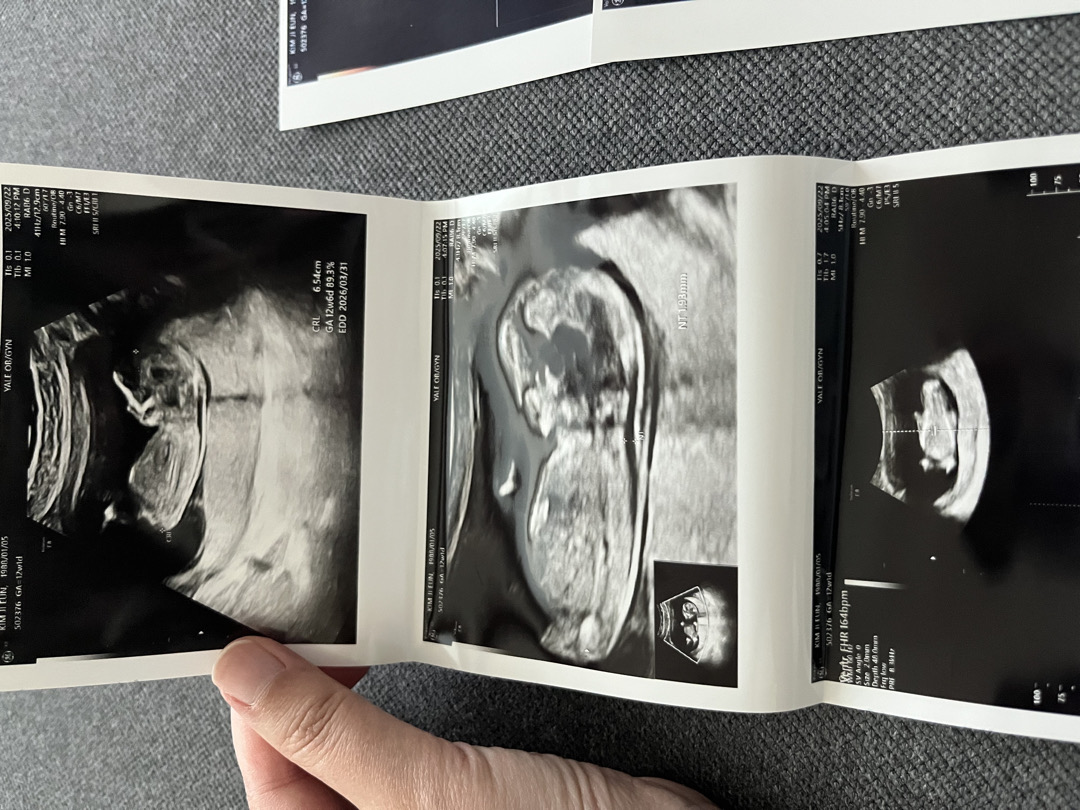

12주 1일차 각도법 봐주세요~~

지금은 4일찬데 12주 1일차 때 찍은 초음파 사진이에요 영상으로 보면 아들 같기도 한데 사진은 딸 같고 성별 너무 궁금하네요~!